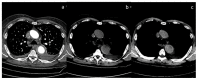

Dual-energy computed tomography (DECT) is one of the most promising technological innovations made in the field of imaging in recent years. Thanks to its ability to provide quantitative and reproducible data, and to improve radiologists' confidence, especially in the less experienced, its applications are increasing in number and variety. In thoracic diseases, DECT is able to provide well-known benefits, although many recent articles have sought to investigate new perspectives. This narrative review aims to provide the reader with an overview of the applications and advantages of DECT in thoracic diseases, focusing on the most recent innovations. The research process was conducted on the databases of Pubmed and Cochrane. The article is organized according to the anatomical district: the review will focus on pleural, lung parenchymal, breast, mediastinal, lymph nodes, vascular and skeletal applications of DECT. In conclusion, considering the new potential applications and the evidence reported in the latest papers, DECT is progressively entering the daily practice of radiologists, and by reading this simple narrative review, every radiologist will know the state of the art of DECT in thoracic diseases.